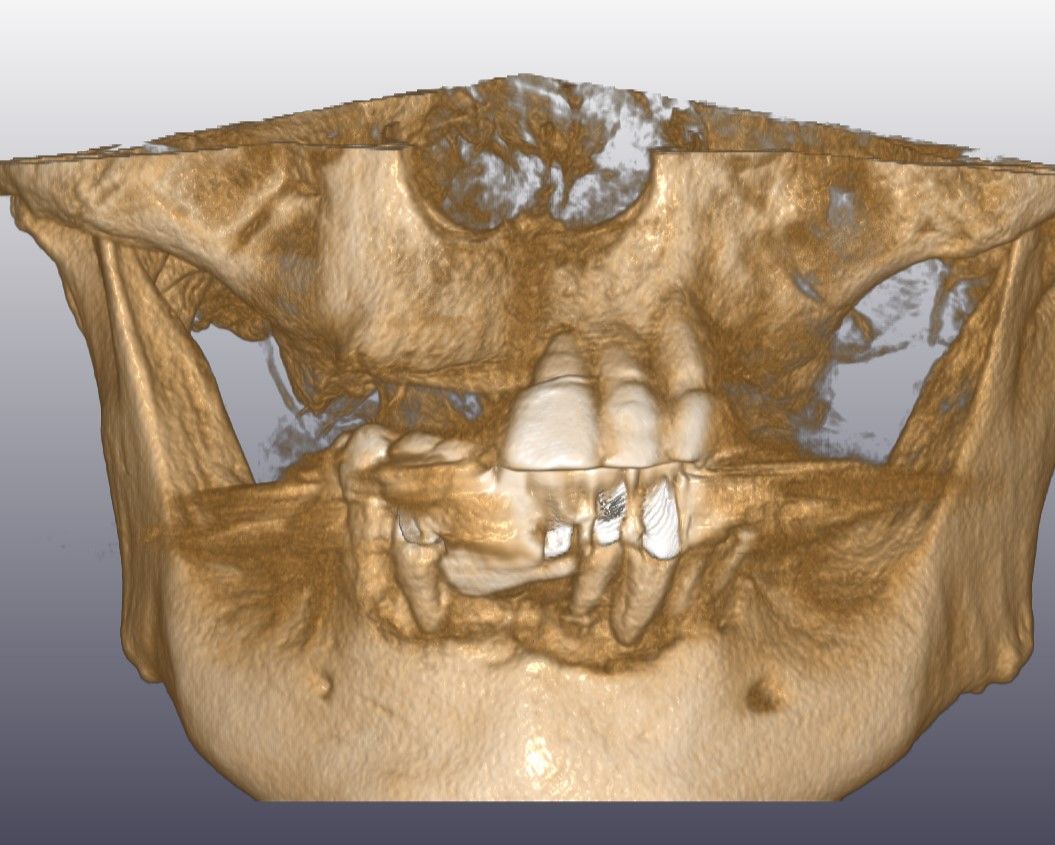

先日インプラントの型取をした患者さんの被せ物が出来上がってきました。

これをネジを使ってインプラントに接続します。